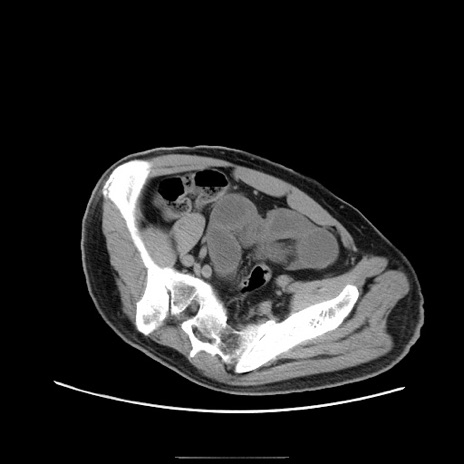

症例22(横断像)

【症例】50歳代男性

【主訴】腹痛

【現病歴】AVMからの被殻出血のため回復期リハ病棟入院中。 本日午後3時頃急に下腹部痛が出現した。

【既往歴】AVM、被殻出血、虫垂炎、高血圧

【身体所見】意識晴明、左半身不全麻痺、会話の理解は良好、36.5°C、腹部:膨隆、全体に板状硬、下腹部正中に圧痛点あり、反跳痛-、筋性防御不明、右下腹部にope scar

【データ】WBC 9400、CRP 0.06